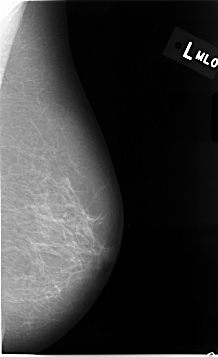

C_0014_1.LEFT_MLO

C_0014_1.LEFT_CC

LEFT_CC LINES 4648 PIXELS_PER_LINE 2696 BITS_PER_PIXEL 12 RESOLUTION 50 NON_OVERLAY

LEFT_MLO LINES 4632 PIXELS_PER_LINE 2824 BITS_PER_PIXEL 12 RESOLUTION 50 NON_OVERLAY